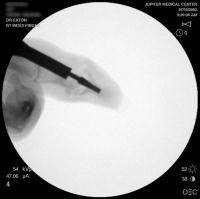

Intraoperative fluoroscopy.

Broach.

The trial implant sizer shows the true size of the implant. The final implant has a radiolucent coating  which makes it appear smaller than it is on Xray.